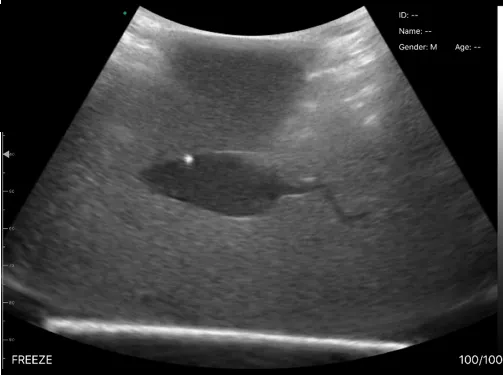

Professor Carmel Moran and University of Edinburgh researchers delivered a public outreach activity on preclinical imaging to a Scouts group. Image Ultrasound image of the object embedded in gel. On the 10th March 2022, imaging expert Professor Carmel Moran, along with Dr David Hardman (Usher Institute) and Xanthe Miller (MPhys UG student), delivered a public outreach activity to the group of 20 Scouts at Craigmillar Park Church Hall. Their scout leader is Dr Natalie Homer. The activity entitled ‘Imaging Inside-Out’ involved a hands-on experience where participants used lightweight hand-held ultrasound scanners of varying frequencies to obtain live images of 3D printed miniaturised 3D shapes and mice embedded at different orientations in opaque gels. This activity encouraged a lively and informed discussion between the Scouts and University of Edinburgh researchers about medical imaging and the use of animals in research. The participants reflected back on what they learnt and gave positive feedback, such as ‘good’, ‘curious’, and ‘happy’, about their experience during the activity. The activity was funded by Professor Carmel Moran's ScotPEN Wellcome Engagement Award. To view more photos from the 'Imaging Inside Out' Scouts evening, please click here. Relevant links Professor Carmel Moran Dr David Hardman Dr Natalie Homer Centre for Cardiovascular Science (CVS) Usher Institute CVS news article Edinburgh Imaging Edinburgh Preclinical Imaging What is an Ultrasound scan? Social media tags and titles Professor Carmel Moran and University of Edinburgh researchers delivered a public outreach activity on preclinical imaging to a Scouts group. @EdinUniMedicine @EdinUniCVS @CarmelIMMoran1 @EdinUniUsher Publication date 30 Mar, 2022